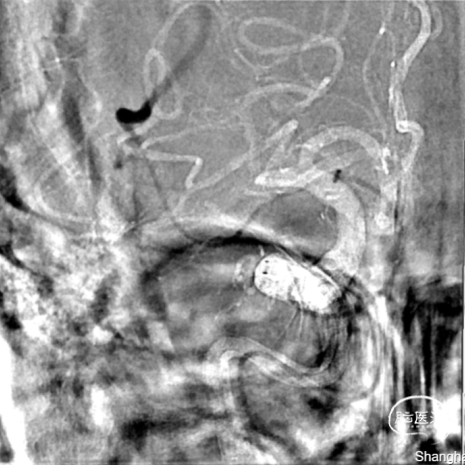

DSA:右侧大脑中动脉M1段闭塞。

微导丝带微导管通过闭塞部位至M2段,造影确认真腔。

释放4mm*25mm NeuroHawk取栓支架嵌合血栓,将X-track颅内远端导管头端置于血栓近端。

抽拉结合,一把取栓实现mTICI 3级再通。